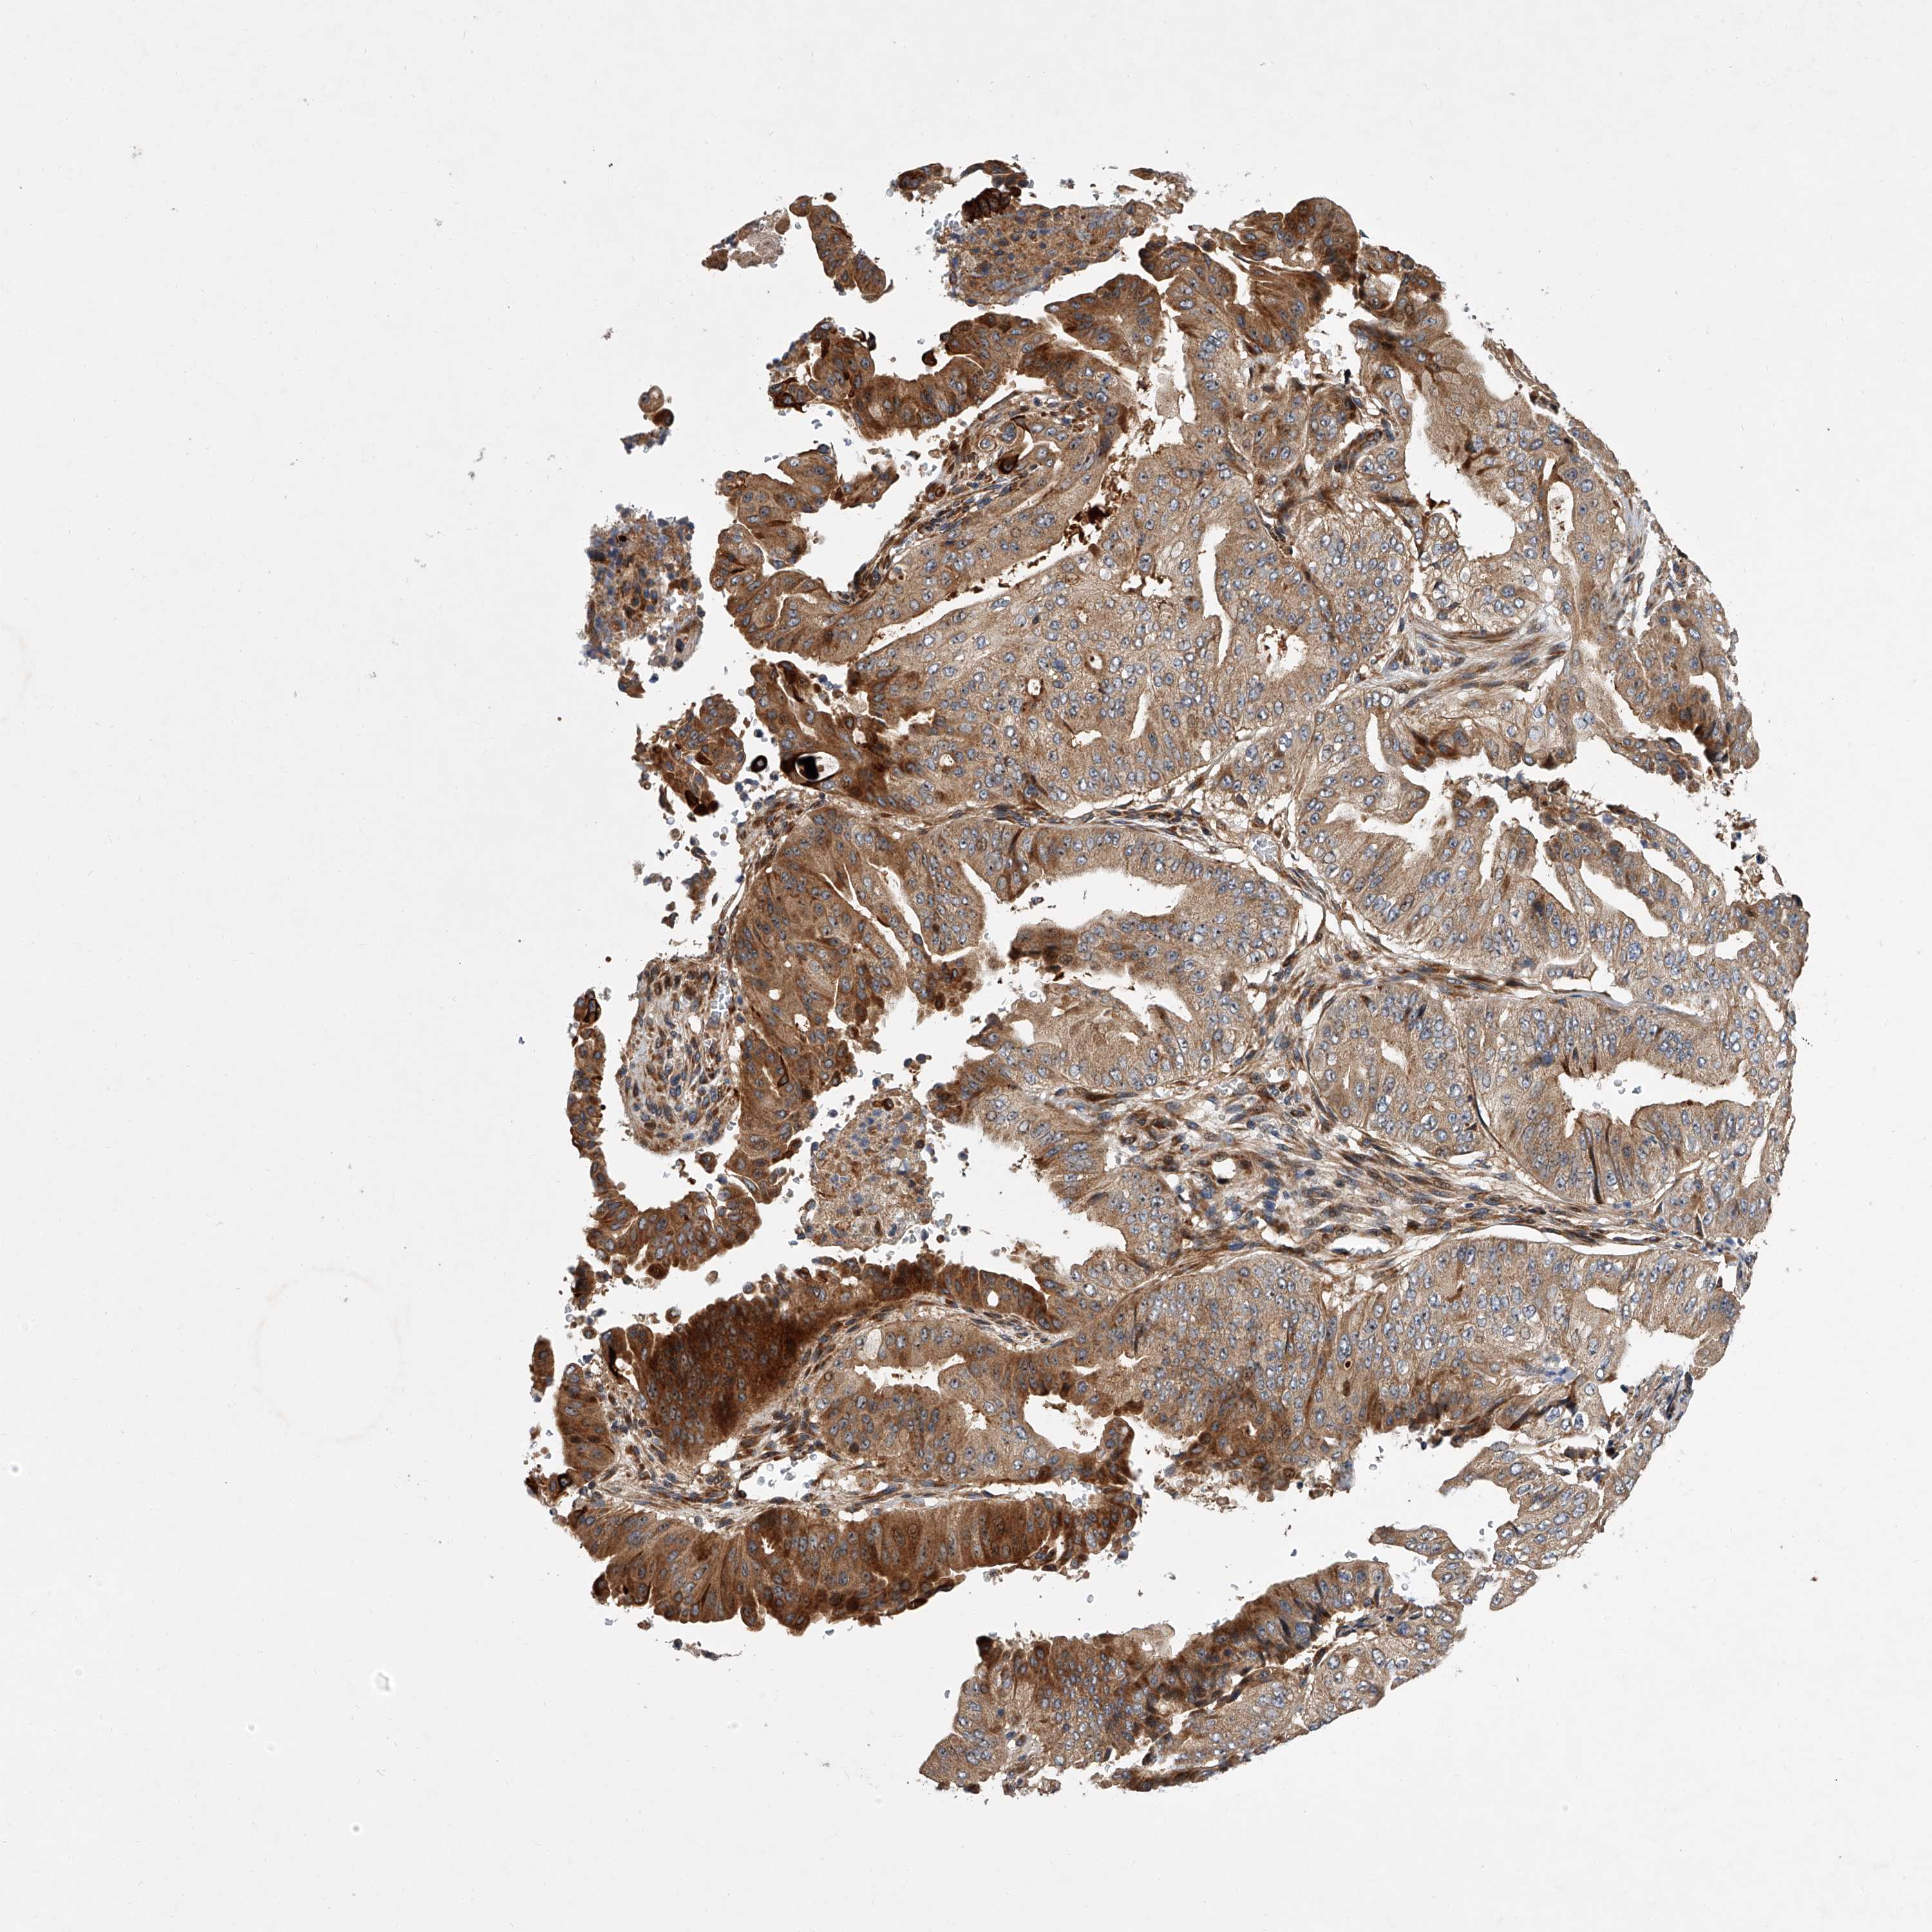

PANCREATIC CANCER - Protein expressioni

A mouse-over function shows sample information and annotation data. Click on an image to view it in a full screen mode. Samples can be filtered based on level of antibody staining by selecting one or several of the following categories: high, medium, low and not detected. The assay and annotation is described here.

Note that samples used for immunohistochemistry by the Human Protein Atlas do not correspond to samples in the TCGA dataset.

Antibody stainingi

Antibody staining in the annotated cell types in the current human tissue is reported as not detected, low, medium, or high, based on conventional immunohistochemistry profiling in selected tissues. This score is based on the combination of the staining intensity and fraction of stained cells.

Each image is clickable and will lead to virtual microscopy that enables deeper exploration of all samples and also displays staining intensity scores, fraction scores and subcellular localization as well as patient and tissue information for each sample.

Antibody HPA029286

Antibody HPA029289

Adenocarcinoma, NOS